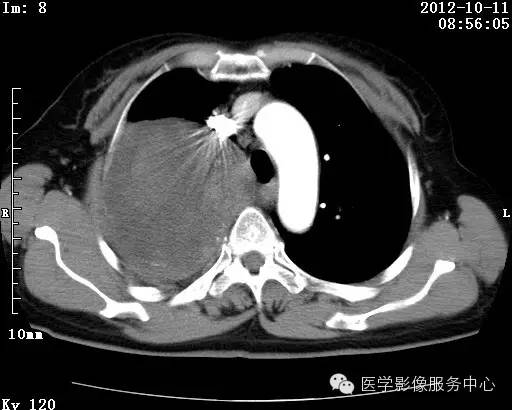

【病例】右肺巨大错构瘤1例CT影像表现

病史:女 65岁咳嗽咳痰 右肺巨大肿块就诊。

错构瘤的主要组织成分包括软骨、脂肪、平滑肌、腺体、上皮细胞,有时还有骨组织或钙化。错构瘤一般为实质致密的球形、卵圆形,也可以是分叶状或结节状,大多数直径在3cm以下。

错构瘤的发病年龄多数在40岁以上,男性多于女性。 绝大多数错构瘤(约80%以上)生长在肺的周边部,紧贴于肺的脏层胸膜之下,有时突出于肺表面。其特征钙化为爆米花样钙化,内有脂肪软骨成分等等。最常见的部位是胸膜下肺实质内,其次为主支气管或肺叶、肺段支气管内。

瘤内出现“爆米花样钙化”是诊断的主要指标之一。早期的点状、斑片状及结节状钙化 随时间增加钙化数量及范围会增加,最终可能演变 为爆米花样钙化;

另一项主要指标是瘤测得脂肪成分是诊断错构瘤。